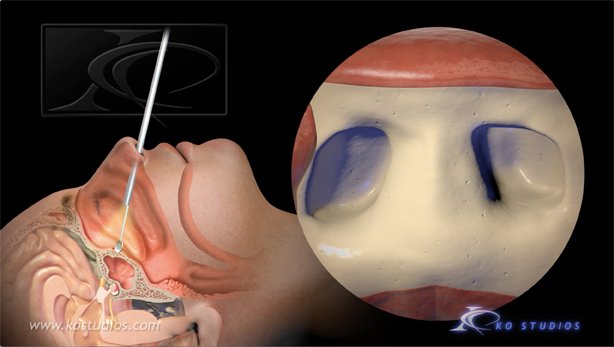

Endoscopic Pituitary Surgery-Nasal Approach

“A pituitary tumor is an abnormal growth of cells within or around the pituitary gland. Most pituitary tumors are non-cancerous growths called adenomas, which do not spread to other parts of the body. However, pituitary adenomas can cause the pituitary gland to produce too many or too few hormones, causing a variety of symptoms.”

This animations depicts tumor removal via the nasal approach.

Copyright©2021: BNI, Authors: KO Studios,

Narration: Dr. Andrew Little

https://www.barrowneuro.org/condition/pituitary-tumors/